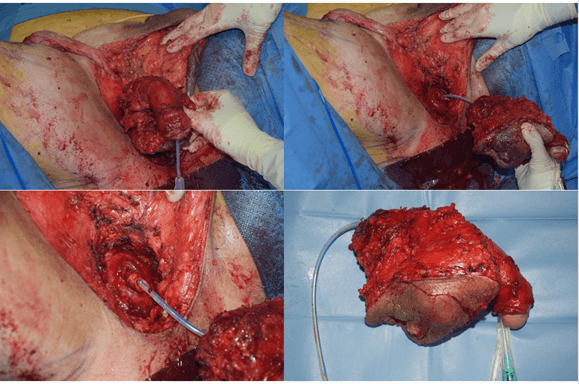

Phase I: The patient is placed in a forced lithotomy position, and an incision is made with a cold scalpel on the limits of the mass in the cutaneous plane (Figure 5). The bulbar urethra and the corpora cavernosa are removed from their roots. Penile degloving is performed, and the penis is extracted through the perineal incision, thus achieving an en bloc removal of all tumor tissue (Figure 6).

Figure 6: En bloc excision of tumor tissue with total penectomy. The remaining healthy urethra segment corresponding to the membranous urethra, and proximal to it, the prostatic apex, can be seen.

The surgical specimen corresponds to a 16.5x11x9cm penectomy piece, consisting of penis and perineum. It shows a 10.5cm solid mass with whitish cut surface and infiltrative borders. This tumor is localized in perineum and it ulcerates the skin and reaches the base of the penis and cavernous bodies (Figure 10). Histological study reveals a moderately differentiated squamous cell carcinoma with keratinization and pleomorphic areas. The tumor shows neurotropism and frequent mitotic figures. The surgical edges were not compromised.

Figure 10: Macroscopic view of penectomy specimen. A large perineal ulcer is seen (arrow). The tumor reaches the base of the penis and cavernous bodies (asterisks).